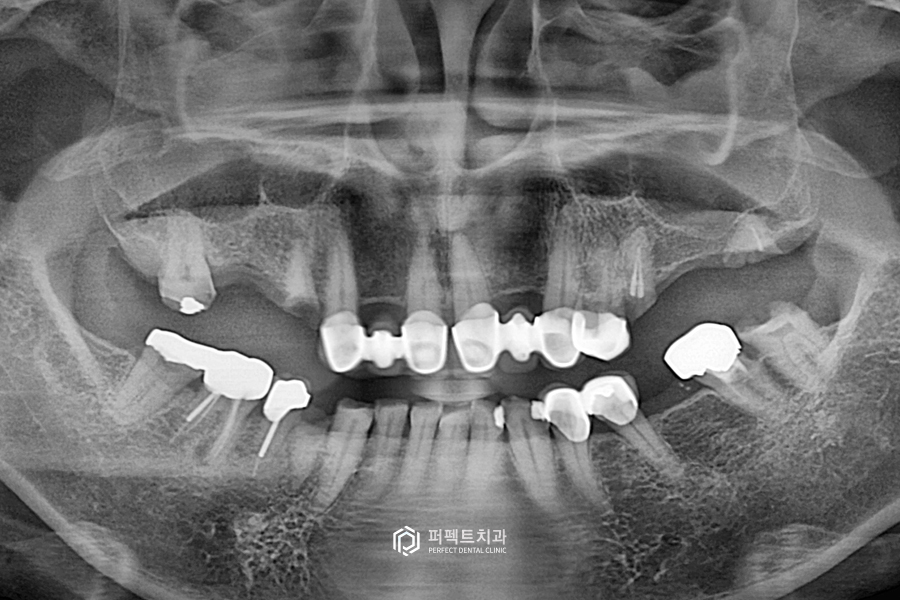

치료 후 사진을 보시면 임플란트가 오른쪽 위에 2개, 왼쪽에 1개, 아래 2개 이렇게 치아가 없는 부위를 수복했습니다. 임플란트가 없는 왼쪽 어금니 부분은 기다렸다가 추후에 식립을 진행했습니다.

왼쪽 임플란트가 없었던 부분에 하나 더 식립을 했습니다. 왼쪽 어금니를 식립한 부분은 상악동이라고 하는 곳이 있는데 이 부분에 뼈가 없어서 기다렸다가 추후에 식립한 경우라고 보시면 될 것 같습니다.

이렇게 어금니는 총 7개의 임플란트를 식립했고, 앞니 보철과 아랫니 부분도 꼭 해야하는 부분은 다시 재치료를 했습니다.

없는 치아들은 임플란트를 통해 수복을 했고 위, 아래 사랑니도 발치를 하였습니다. 그리고 마찬가지로 앞니 부분 옛날 보철들을 지르코니아 크라운으로 교체를 했습니다.